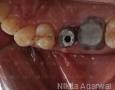

Surgery

3 Months

4 Months

6 Months

1 Year